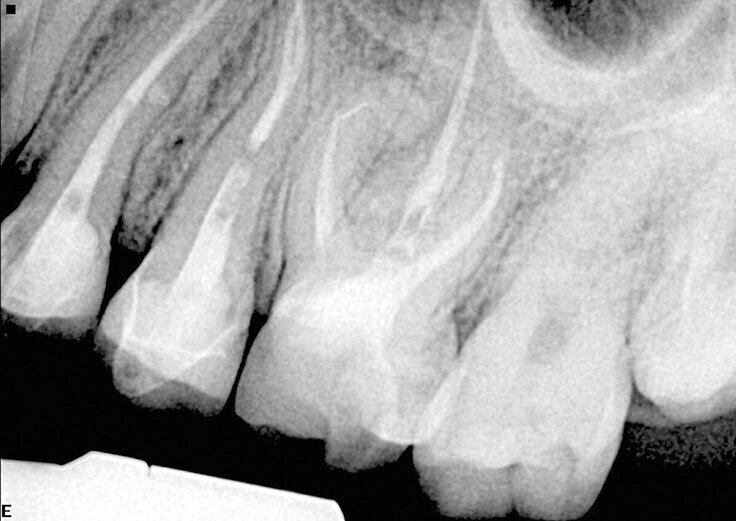

Slučaj 3 – Slika br. 7: Inicijalni periapikalni Rtg snimak

Slučaj 3 – Slika br. 8: Preoperativni CBCT sken

Poslednji slučaj o kome bih želeo da govorim u ovom članku, jedan je od najizazovnijih tretmana. Pacijentkinja je upućena iz inostranstva na remont gornjeg molara jer je insistirala na spasavanju zuba. Na malom rendgenskom snimku (Slika br. 6) sam jasno video da imamo separisan instrument u mezijalnom korenu, ali je anatomija bila veoma sumnjiva. Pacijentkinja mi je dala CD sa CBCT urađenim za nju, i gledajući različite delove , mada bih više voleo veću rezoluciju snimka (Slika br. 7), primetio sam 3 različita izlaza za mezijalni koren sa veoma neobičnom anatomijom. Proučavajući ovaj slučaj primetio sam i grananje na palatinalnom korenu u apikalnoj oblasti. Objasnio sam pacijentkinji da ću dati sve od sebe da joj spasem zub. Koristio sam istu sekvenca turpija Traverse i Zenflex u distalnom i palatalnom kanalu korena zuba do pune radne dužine, a kod mezijalnog korena sam dostigao do zalomlejnog instrumenta i prešao na veoma delikatan zadatak njegovog zaobilaženja i obrade ovog veoma složenog sistema korenskih kanala. Slika br. 8 prikazuje neposrednu postoperativnu i 3D obturaciju mezijalnog kompleksa, kao i palatinalno grananje. Slike br. 9 i 10 su nakon 12 i 18 meseci od tretmana gde se vidi dobro zarastanje i svaki put kada uzmem da pogledam iz drugačijeg ugla vidim složenost mezijalnog korena.